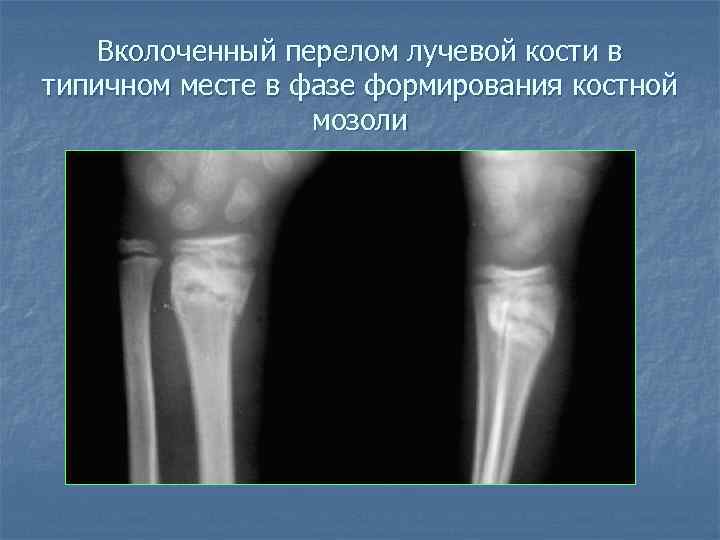

Вколоченный перелом лучевой кости в типичном месте

Вколоченный перелом лучевой кости в типичном месте в фазе формирования костной мозоли